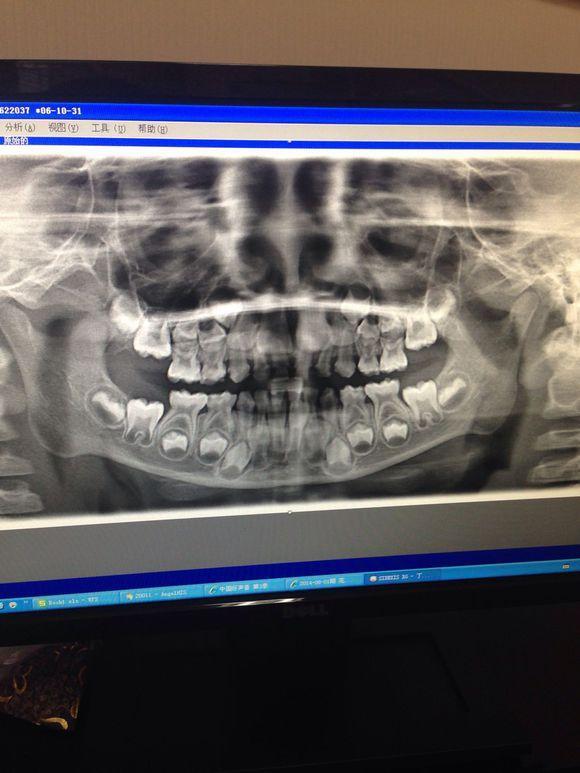

孩子在6-7岁的时候,乳牙换成恒牙,换牙后就伴随着一生,很多父母会奇怪,宝宝的牙齿是怎么生长出来的呢?其实在乳牙还未脱落时,恒牙胚就已经在慢慢发育长大,那么此时的宝宝牙齿是什么样的呢?现在发出几张换牙时的照片,这样会有更直接的了解。

可以看出还未长出的恒牙胚,正在逐渐发育,慢慢向外生长。

这是换牙期颅骨的侧面照,可以看出,如果宝宝乳牙未脱落,恒牙就长出,出现双层牙是多么恐怖是事情。